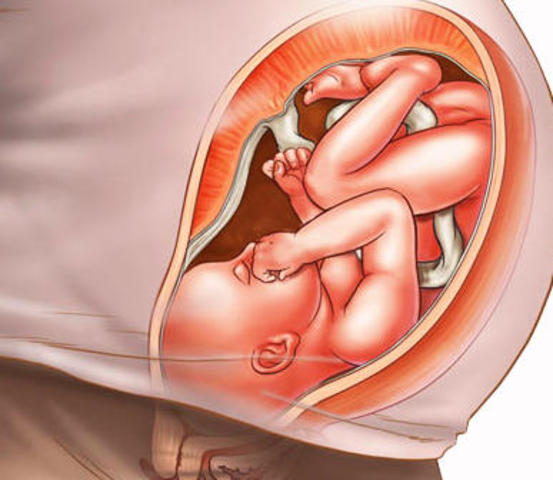

La posición habitual es semiflexionada con las manos a la altura de la barbilla y los pies cruzados por debajo de la salida del cordón umbilical.

Tu hijo flota en el agua, ya que todavía el saco amniótico es muy espacioso. Esto permite al bebé moverse de un lado a otro, darse la vuelta, girarse, dar patadas y cambiarse de posición varias veces en un día.

A esta edad gestacional, la mayoría de los niños se sitúan con la cabeza hacia abajo (en la llamada posición cefálica), por lo que las patadas se notan en la parte alta del abdomen.

Esta posición cabeza abajo todavía puede variar, aunque generalmente ya no se modifique porque los movimientos van siendo más limitados: el útero es cada vez más pequeño para el bebé.

Ya suele estar colocado cabeza abajo, lo que denominamos presentación cefálica.

Sus movimientos son más limitados, y sobre todo son los miembros inferiores y superiores, los que mueve con más frecuencia. Cada vez es más grande y tiene menos espacio para girar de un lado a otro o de arriba a abajo.